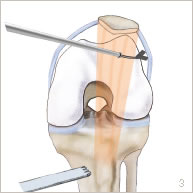

Une section de l’aileron rotulien est d’abord réalisée sous arthroscopie, c’est à dire sans ouvrir l’articulation. Deux petites incisions de 5 mm chacune sont réalisées en avant du genou. Une petite caméra est introduite par l’une d’entre elles pour visualiser l’articulation. Des petits instruments sont introduits par l’autre incision pour sectionner l’aileron rotulien externe (figures 3 et 6).

Par la suite, une incision d’environ 5 cm est réalisée à la partie supérieure du tibia. La tubérosité tibiale antérieure est exposée puis sectionnée (figure 3). Elle est ensuite translatée et repositionnée au milieu du tibia puis fixée par deux vis (figures 4 et 7).